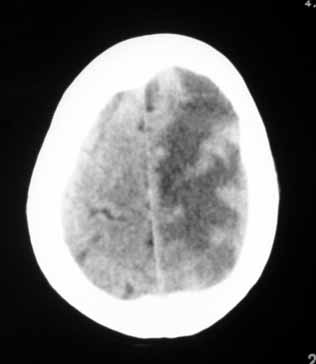

标题: CT9246:转移瘤,有结肠癌手术史. [打印本页]

标题: CT9246:转移瘤,有结肠癌手术史.

1、右侧外囊区脑软化;

2、左侧额、顶、枕区脑转移瘤。

典型的“转移瘤”。

(多发 小病灶,大水肿!)

脑内多发结节性小病灶,周围水肿明显,结合结肠癌病史,典型的转移瘤。